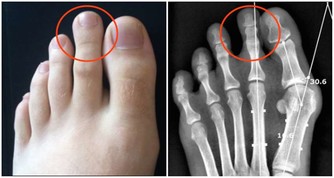

從理論上講,肛腸角越大,直腸越直,排便就越順暢,因此可採用蹲姿,或坐姿時在腳下墊個小板凳;